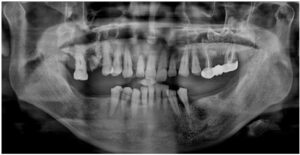

정밀한 검사를 위해

파노라마 사진을

촬영해 보았더니

치아를 단단하게 잡고 있어야 할 잇몸뼈가

녹아내려앉아있고,

염증이 있는 치아들도 다수 보였는데요.

모든 치료가 마무리된

구강 내 사진과

파노라마 사진인데요.